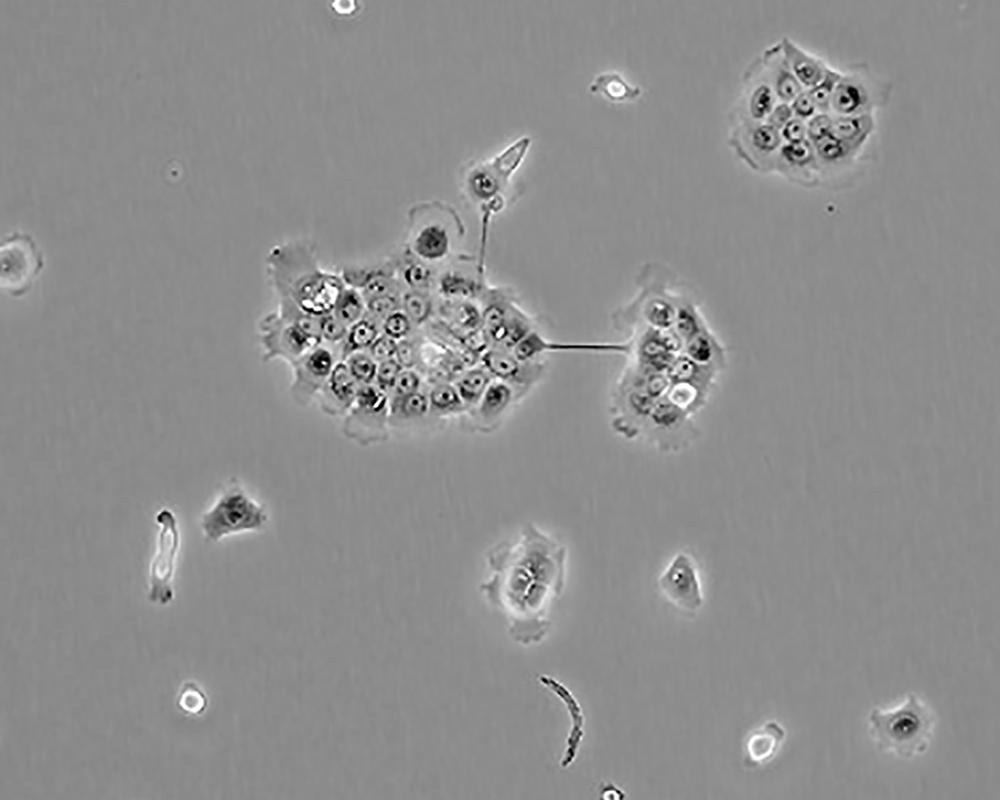

BxPC-3(BxPC3)

產品名稱 BxPC-3(BxPC3)

中文名稱 人原位胰腺腺癌細胞

組織來源 胰腺導管腺癌;女性

生長特性 adherent

形態特征 epithelial

細胞描述 The cells do not express the cystic fibrosis transmembrane conductance regulator(CFTR). A CFTR positive pancreatic line, Capan-1 is available.